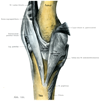

B. 自由上肢の連結

手の関節